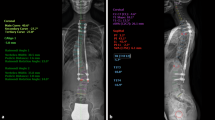

Fourteen patients of this case series finished treatment, so far. Nine received final fusion and five received rod removal without spinal fusion. Within this group the mean Cobb angle was 53.7° (± 7.9) preoperatively and 31° (± 12.9) at final follow-up. The average length of MCGR treatment was 36 months (range: 16–78 months). In those patients who finished treatment the mean T1–T12 height increased 42.5 mm (± 24.3) and the mean T1–S1 height increased 61.1 mm (± 11.6). Due to maximum distraction of the implant one patient received two planned rod exchanges, six patients received one planned rod exchange, and seven patients finished treatment with the first MCGR device. Average time of distraction with one MCGR device was 22.8 months (± 1.1). Figures 4 and 5 show two exemplary cases: one for final fusion (Fig. 4) and one for rod removal without spinal fusion (Fig. 5).

a A 9 year-old girl with a 57° thoracic idiopathic scoliosis. b The same patient after MCGR implantation. c Nine months after implantation the left rod failed to distract and thus the rods were exchanged. d After another 21 months of distraction final fusion was performed resulting in a 46° thoracic curve. The patient is stable at final follow-up